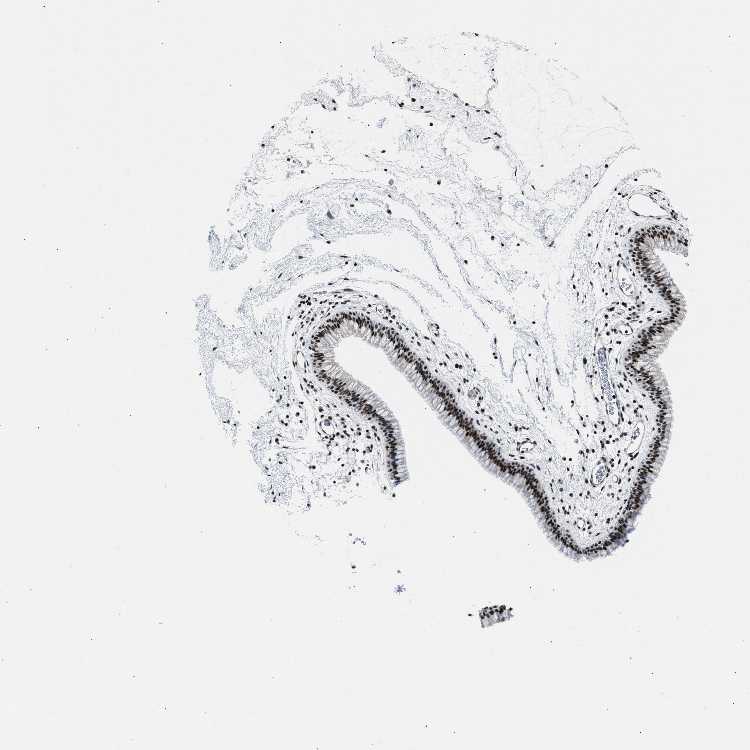

TISSUE PRIMARY DATA NASOPHARYNX Show tissue menu

NASOPHARYNX - Antibody stainingi

Antibody staining in the annotated cell types in the current human tissue is reported as not detected, low, medium, or high, based on conventional immunohistochemistry profiling in selected tissues. This score is based on the combination of the staining intensity and fraction of stained cells.

Each image is clickable and will lead to virtual microscopy that enables deeper exploration of all samples and also displays staining intensity scores, fraction scores and subcellular localization as well as patient and tissue information for each sample.

Antibody HPA018248Antibody HPA019127Antibody CAB009196

Respiratory epithelial cells HighHighMedium